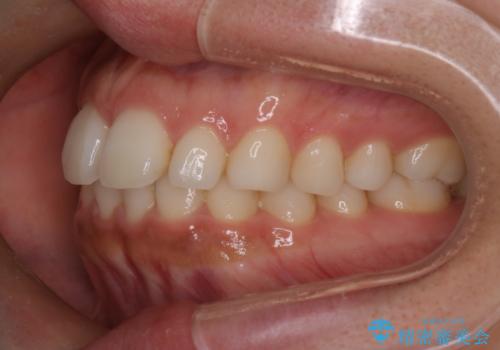

【インビザライン】前歯の後戻りを再矯正

- 前歯が出ていることを主訴に来院されました。検査の結果、口元が標準より出ているわけではなかったため今回はIPRと拡大をし、非抜歯で治療を行いました。

非抜歯でも歯軸の向きを改善したことで前歯が下がり、出っ歯に見えてしまうという主訴が改善しました。